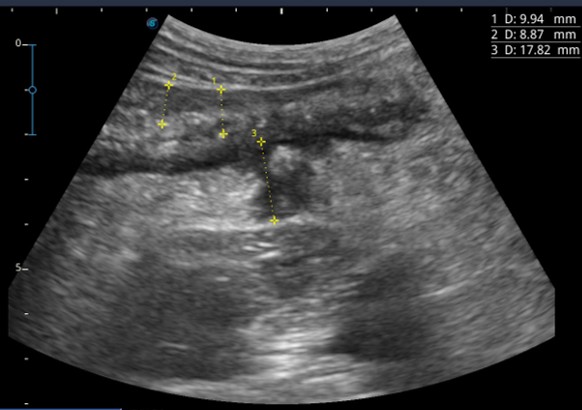

Трансабдоминальное ультразвуковое исследование кишечника как неинвазивный метод диагностики: подготовка, техника, интерпретация

Ультразвуковые признаки болезни Крона, ультразвуковые индексы для оценки активности болезни Крона

Ультразвуковое исследование для выявления осложнений воспалительных заболеваний кишечника